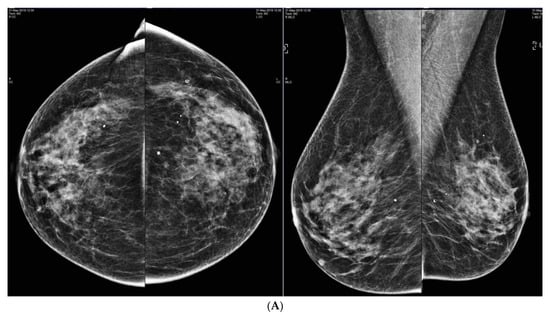

6. Digital Breast Tomosynthesis (DBT)